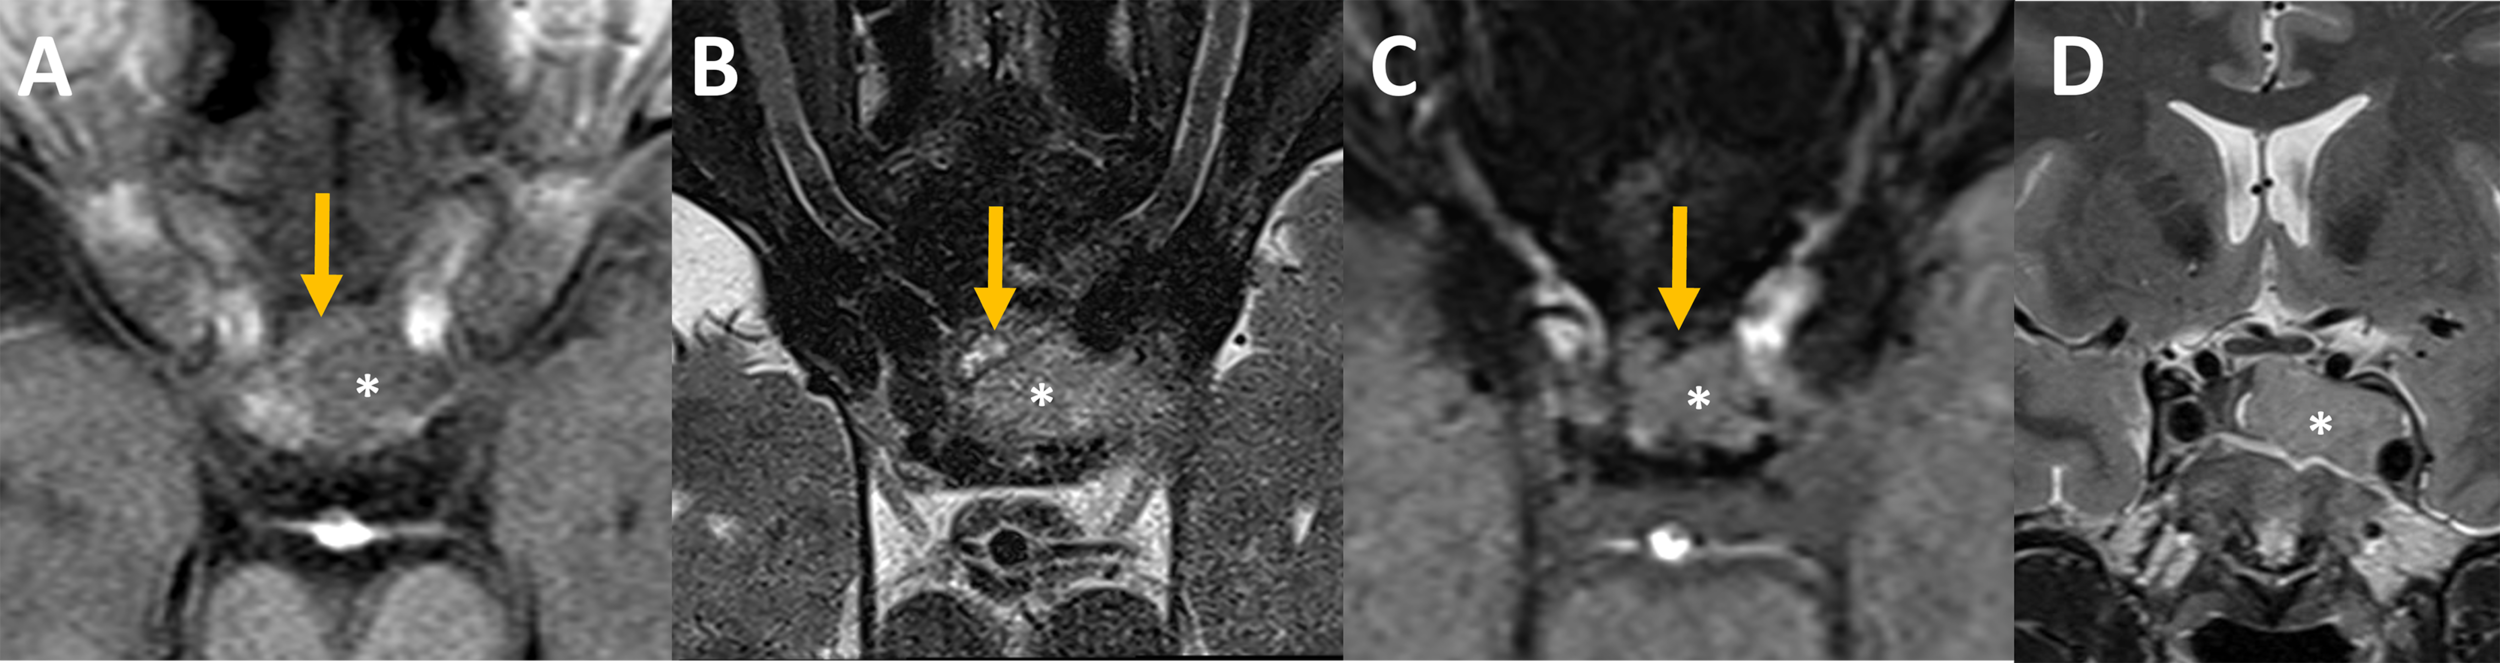

The initial MRI showed a sellar lesion with an invasion of the left cavernous sinus classified 3b according to Knosp classification (17). A heterogenous anterior aspect of the lesion compatible with hemorrhagic zones was in favor of PA and normal pituitary gland was displaced on the right side Figure 2.

Figure 2

Pre-operative MRI Axial MR imaging focused on the sella at admission (A–C): The intra-sellar lesion (star) was heterogeneous on its anterior aspect. Some bloody components (orange arrows) that appeared slightly hyperintense on unenhanced T1 (A), hyperintense with an hypointense rim on T2 spin echo (B) and hypointense on susceptibility weighted images, SWI, (C) were intercalated between the bone and the rest of the lesion. (D) Coronal MR imaging showed pituitary adenoma with invasion of the left cavernous sinus, grade 3b according to Knosp classification (17).